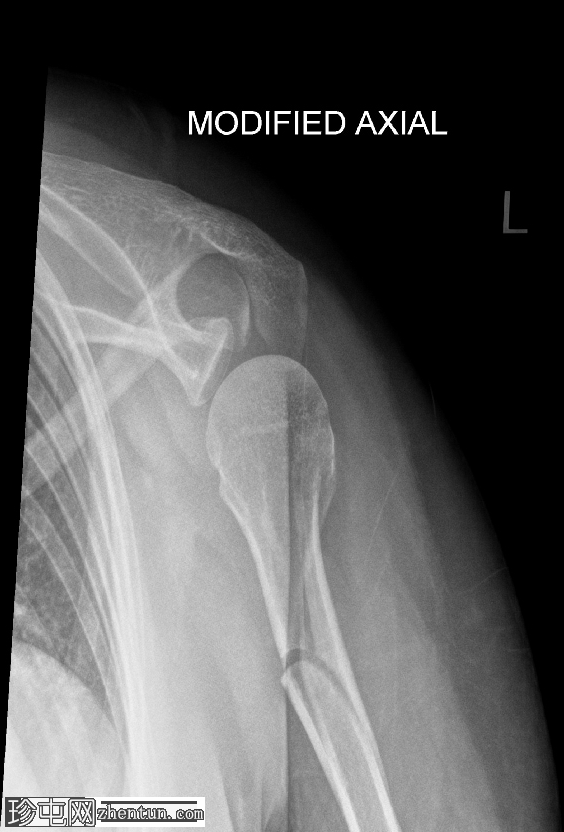

4.png

肱骨近端粉碎性移位骨折,累及骨干近端半部、外科颈,并延伸至大结节。

肱骨头在肩关节内向下半脱位,肩峰肱骨间距增大。

这种表现不应与真正的肩关节脱位混淆,因为在Y形位或轴位影像上,肱骨头仍与肩胛盂保持正确的对位。随着关节液的吸收和肌肉张力的恢复,这种情况通常会自行缓解。识别这种暂时性的良性表现对于避免不必要的复位手术至关重要。